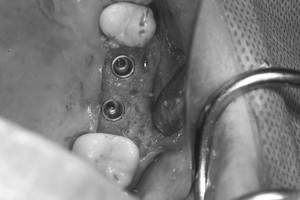

インプラント治療の症例4

レントゲン写真

- Befor

- After

口腔内写真

| 年齢 | 50代・男性 |

|---|---|

| 主訴 | 部位:左下6番7番 主訴:左下奥歯腫れて痛い。 |

| 治療内容 | 左下6番抜歯、左下6番7番骨造成、インプラント埋入 |

| 治療費 | 合計:1,232,000円 ・内訳 診断料:55,000円 サージカルガイド2本:66,000円 GBR:110,000円×2本 埋入料:165,000円×2本 静脈内鎮静麻酔:77,000円 2次OPE:22,000円×2本 仮歯:55,000円×2本 上部構造(フルジルコニア):165,000円×2本 (2023年1月現在) |

| 治療期間 | 約8ヶ月 |

| リスク・副作用 | リスク・副作用 |

| 治療方針 | 元々支台歯に負荷がかかりやすいとされている延長ブリッジを抜歯し、1本単体でしっかりかめるようにインプラントを2本埋入した。骨吸収も進んでいたため、※GBR法で骨造成を同時に行った。 治療と並行して、全顎的な歯周病治療も行い、今後は歯周病が進行しないよう、こまめにメンテナンスに通っていただく。 |

| 特記事項 | ※1 GBR・・・骨再生誘導法。骨の高さや厚みを人工骨や人工膜などを使用し再生する方法 |

| 担当者所見 | 6番は歯根分割された被せ物が7番の欠損部との延長ブリッジとされており、強い咬合と歯周病も相まって負荷がかかり動揺し、歯として機能しなくなったため、抜歯となった。 |